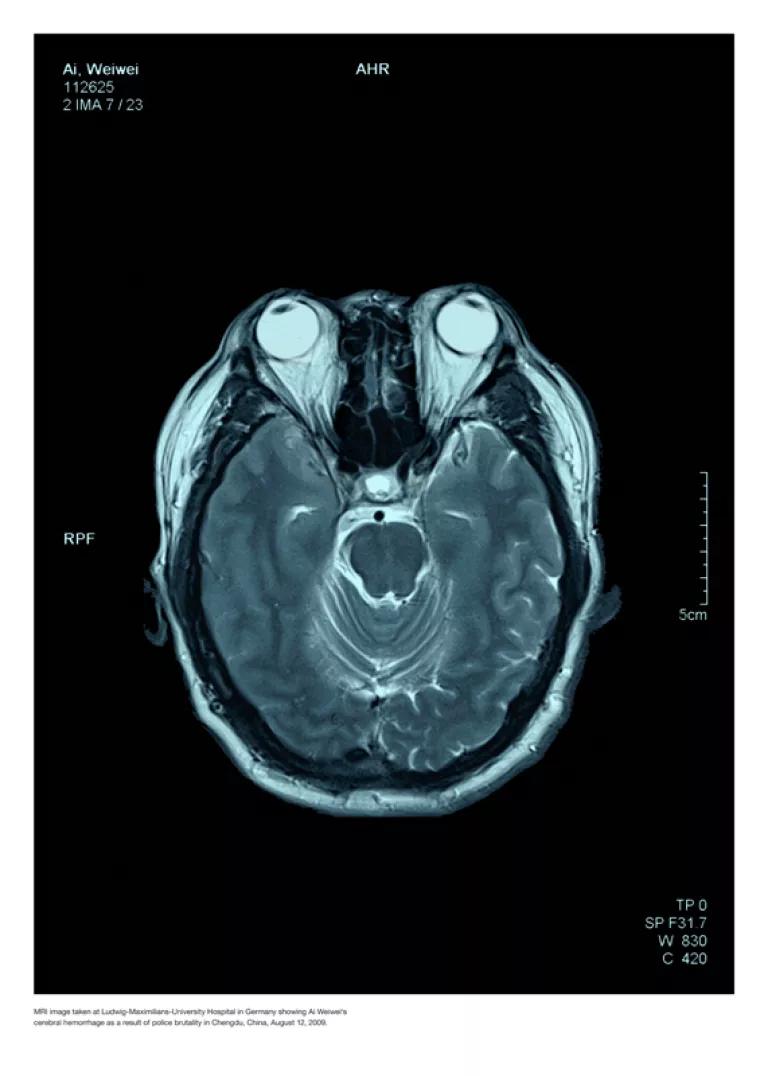

Ai Weiwei – Police Brutality, 2010/2011

Digitaler 11-Farben Pigment-Print einer Computertomographie auf Fabriano Designo Satinato, 50 % Cotton 300 g

Ai Weiwei geb. 1957 in Peking. Der Künstler und Kurator ist Sohn des Dichters Ai Qing. Er studierte an der Filmakademie Peking und ab 1981 an der Parsons The New School for Design in New York. 1993 kehrte er nach Peking zurück, entwarf sich ein Wohnatelier und begann, auch als Architekt zu arbeiten. Teilnahmen an der 48. Biennale Venedig und der documenta XII, weltweite Einzelausstellungen. Mit Jacques Herzog und Pierre de Meuron entwickelte er das Konzept für den „Vogelnest“-Bau des Pekinger Olympiastadions. 2009 wurde er von Polizisten zusammengeschlagen, damit er nicht als Zeuge in einer gerichtlichen Ermittlung zu Pfusch am Bau bei Schulgebäuden aussagen konnte; diese waren bei einem Erdbeben eingestürzt und hatten Tausende von Kindern unter sich begraben. Im September 2009 zeigten sich die Spätfolgen; während eines Aufenthalts in München mußte Ai wegen eines Hämatoms im Gehirn notoperiert werden. Von April bis Juni 2011 war er inhaftiert.

Ai Weiwei - Police Brutality (2010 / 2011)